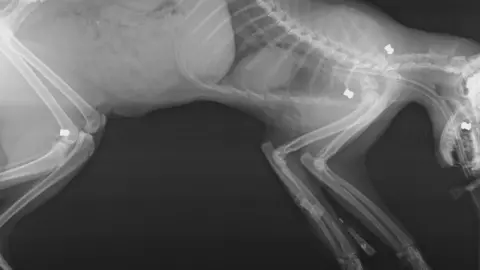

Plymouth Veterinary GroupAn air rifle attack on a cat which lost an eye after being shot five times happened two weeks after a similar attack on the same street.

Vets said one-year-old Bruno must have been "pinned down" and shot in the head, leg and shoulders.

During the operation they discovered an air rifle pellet in his eye socket and four more inside his body.